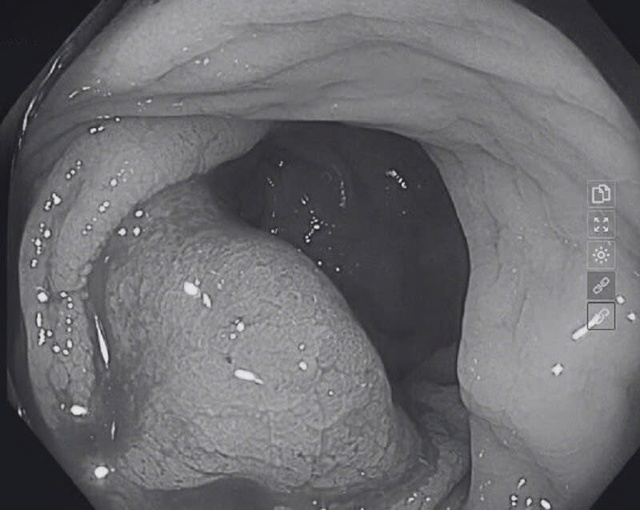

Nội soi đại trực tràng phát hiện khối u chiếm khoảng 2/3 chu vi lòng đại tràng kích thước xấp xỉ 4cm (Ảnh:BVCC).

"Kết quả nội soi dạ dày phát hiện viêm thực quản trào ngược độ A, viêm teo dạ dày (C2) và theo dõi dị sản ruột. Nội soi đại trực tràng cho thấy tại đoạn đại tràng ngang xuống có nhiều polyp kích thước 0,3–0,8cm.

Đặc biệt, ở vị trí trực tràng, cách hậu môn khoảng 10cm, phát hiện một khối u chiếm khoảng 2/3 chu vi lòng đại tràng, kích thước gần 4cm, bề mặt cứng, dễ chảy máu khi chạm vào", BS. Quế nói.